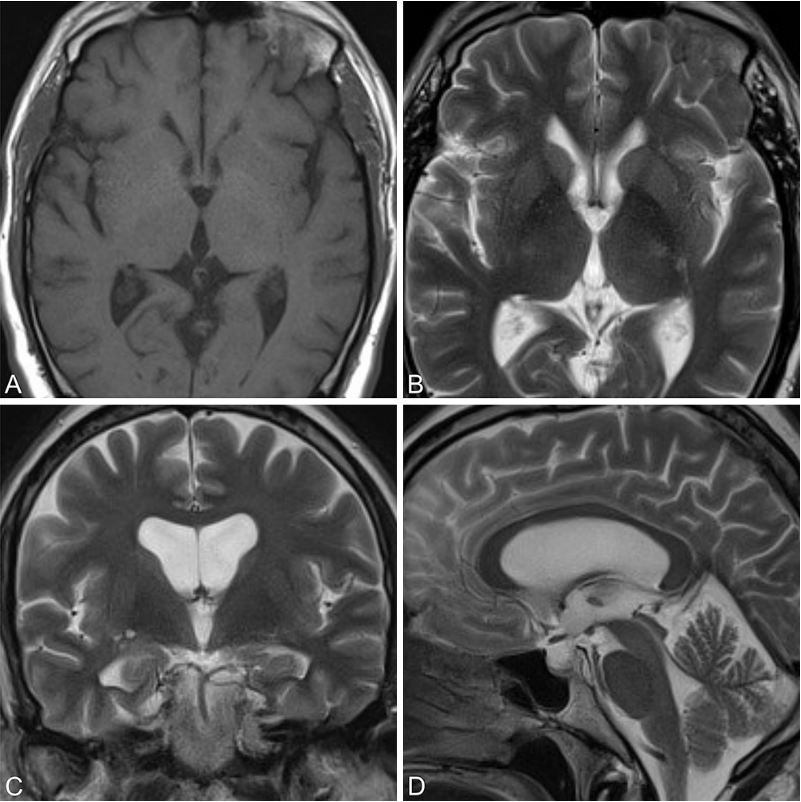

胶样囊肿属于先天性发育异常病变,并非真性肿瘤。该病变囊壁结构包含外层纤维组织和内层上皮组织,上皮内含纤毛细胞及粘蛋白分泌细胞。肉眼观察显示胶样囊肿呈乳白色、去壳荔枝样形态。多数囊肿位于第三脑室前部,处于两侧穹窿柱之间的特殊位置,易导致脑脊液循环通路阻塞,引发梗阻性脑积水,严重病例可能发生猝死。

55岁男性患者因进行性行走障碍和记忆力减退就诊,影像学检查确诊为第三脑室胶样囊肿伴梗阻性脑积水。世界神经外科学会联合会(WFNS)内镜委员会前主席Henry W.S. Schroeder教授主刀施行神经内镜下囊肿切除术。术后三年随访显示囊肿完全切除,无复发迹象。